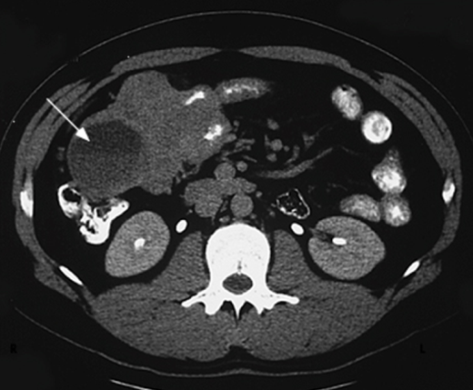

Nazik bağırsağın digər şöbələrinin ikiləşməsi (dupplikasiyası)

Mədə-bağırsaq sisteminin hissələrinin ikiləşməsinin 57%-ni təşkil edir. Əsas etibarı ilə ikiləşmənin qalça bağısaq lokalizasiyası müəyyən olunur (şək 5. ). Təcrid olunmuş ikiləşmə az təsadüf edir. Əksər hallarda digər bağırsaq anomaliyaları, üzvlərin və sistemlərin yanaşı anomaliyaları və inkişaf qüsurları ilə birgə rast gəlir.

Şək. 5. Nazik bağırsağın ikiləşməsi

Diaqnostika. Anamnestik məlumatlar (düz bağırsaqdan periodik qanaxmalar, residiv qarın ağrıları, nəcis ifrazının qəbizliyə meylliliyi), palpator kütlə əllənməsi, kontrastlı RH-ji və KT müayinələri (genişlənmiş proksimal (gətirici) bağırsaq ilgəyi, kontrastın haçalanması, kəskin hallarda üfuqi maye-qaz səviyyələri), laparoskopiya diaqnozun qoyulmasında çox mühümdür.